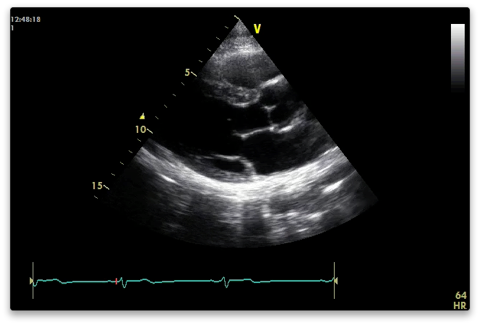

PLAX (Parasternal Long Axis)

2nd to 5th intercostal space just next to sternum. Probe marker pointed towards patient’s R shoulder. The higher the level the more likely the LV will be at 90 for M-mode measurements.

Capture a shallower clip with the heart filling the screen. You are not meant to see the apex of the LV.

RVOT uppermost

Aortic valve - right coronary cusp above; non below

Mitral valve - A2 (upper) and P2 (lower) segments visible

Descending aorta behind posterior MV annulus.